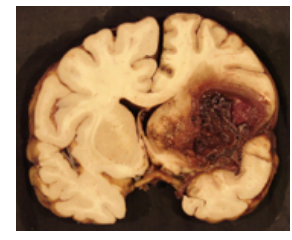

Name the stroke.

Intracerebral hemorrhagic.